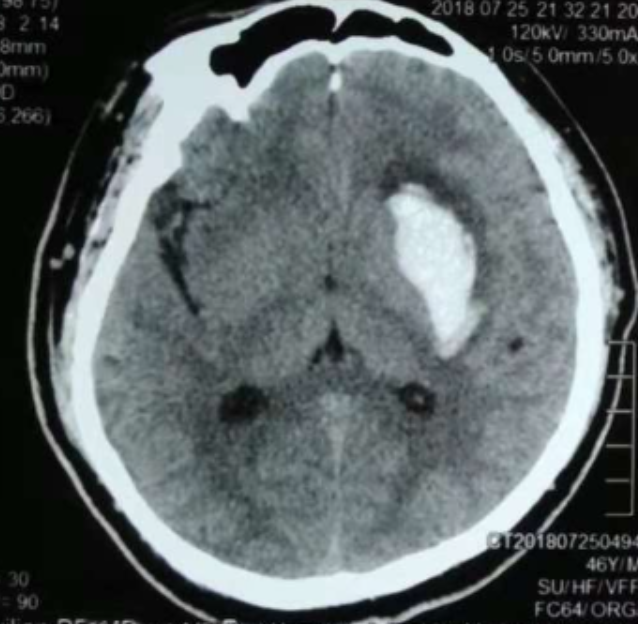

術(shù)后CT:血腫腔消失